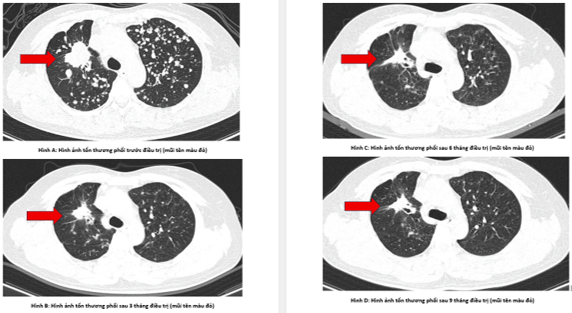

- Chụp cắt lớp vi tính lồng ngực:

Hình 3: Hình ảnh sau các đợt điều trị:  Các tổn thương của phổi (giảm số lượng và kích thước sau các đợt điều trị).

Như vậy, bệnh nhân đáp ứng khá tốt với Gefitinib: chất chỉ điểm khối u, kích thước tổn thương phổi có xu hướng giảm dần.